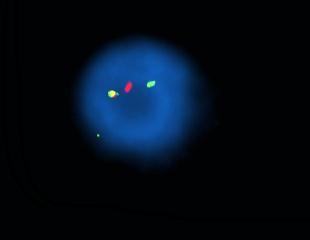

- Cariotipo e hibridación in situ fluorescente (FISH): estas técnicas se utilizan principalmente para detectar alteraciones cromosómicas. El cariotipo es una prueba que consiste en que después de varios días de cultivo celular, los cromosomas se extienden y fijan en un portaobjetos y posteriormente se tiñen. La técnica permite observar al microscopio el conjunto completo de cromosomas de una célula, organizados y ordenados por tamaño, forma y número. Con esta técnica, se pueden identificar anomalías numéricas, como la trisomía 21 en el síndrome de Down y alteraciones estructurales de gran tamaño, como deleciones, duplicaciones, translocaciones o inversiones. Por otro lado, sondas fluorescentes que se unen a secuencias específicas de ADN, permitiendo identificar al microscopio, alteraciones cromosómicas numéricas y alteraciones estructurales de menor tamaño que el cariotipo. Se usa comúnmente en el diagnóstico de síndromes de microdeleción y ciertos tipos de cáncer, como leucemias y tumores sólidos con reorganizaciones cromosómicas específicas. Estas dos técnicas son complementarias, ya que el cariotipo permite un análisis global de los cromosomas, mientras que la FISH aporta una mayor precisión en el diagnóstico de alteraciones a nivel molecular.